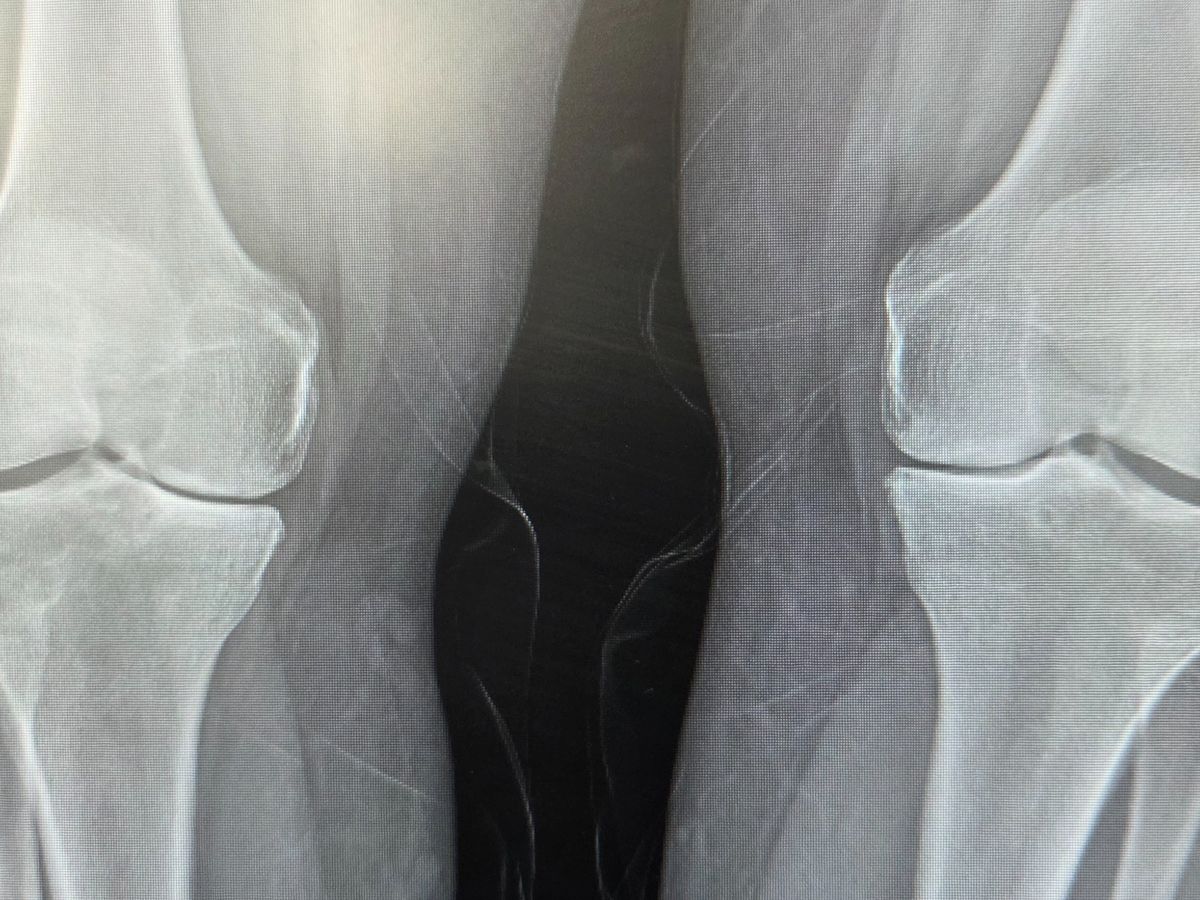

I have to have surgery in two weeks on the 23rd of January for a partial knee replacement on my right knee, and they are wanting me off for up to 12 weeks. After I've healed from that, they are wanting to do the other knee. But I can't even really think about that right now. We are 7 days past due on our rent and struggling to keep other bills paid. We have our kids usually every other weekend, and it's a struggle to make sure we have enough groceries for them. My husband is already working OT, and he is exhausted.